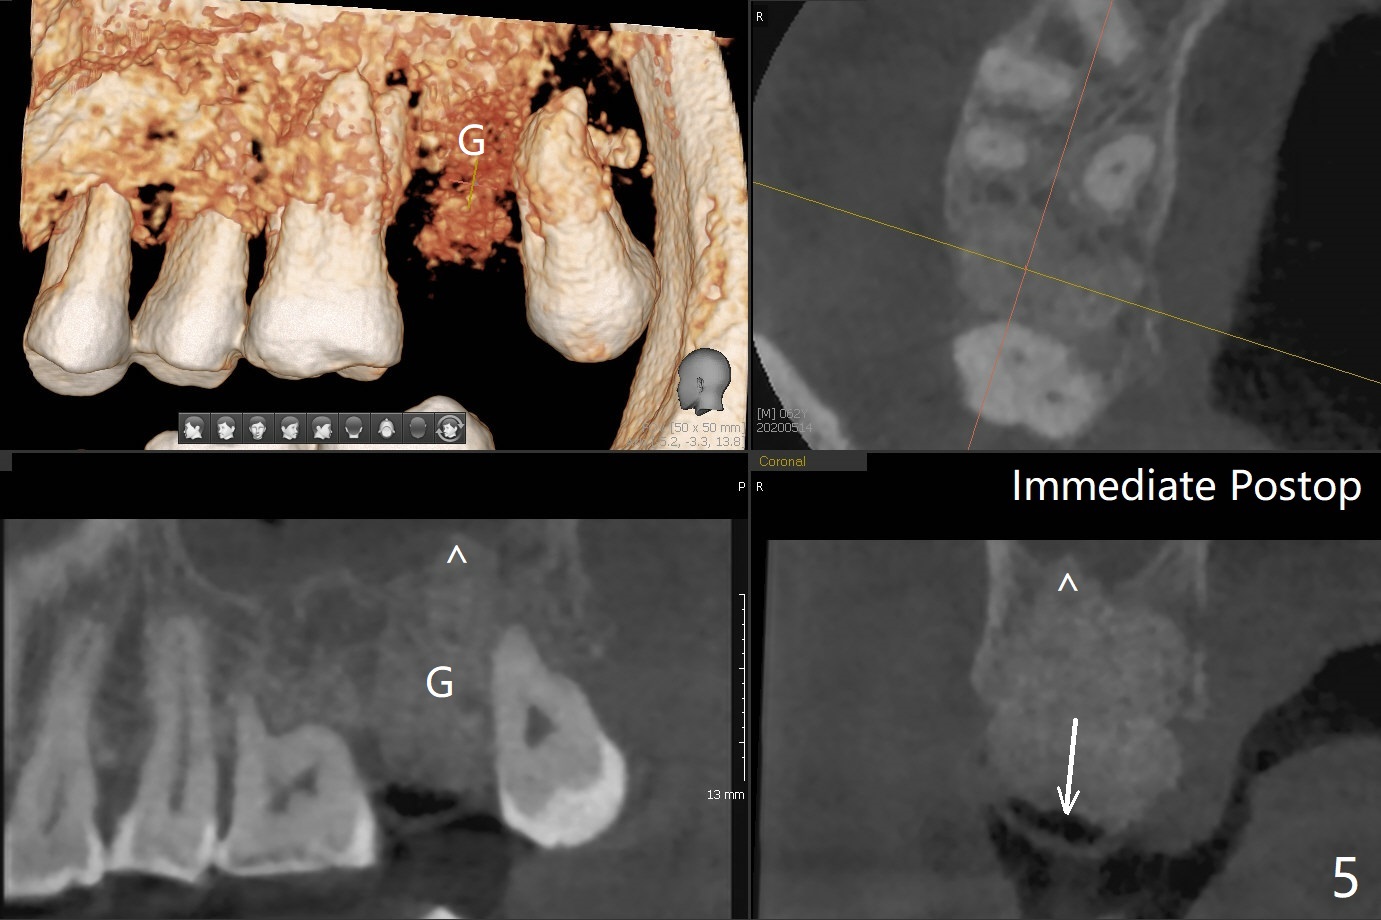

A 62-year-old man has palatal abscess with deep pockets (Fig.1 A) at tooth #2 with DO caries (Fig.2 C). The patient agrees with extraction and bone graft. Preop CT shows the palatal (P) wall defect and buccal (B) socket perforation (Fig.3 *). It should be easy to do sinus lift with the thick sinus membrane (M). To maximize hard tissue regeneration, GEM21S is used to hydrate ground cortical chips (particle size: 125μm – 850μm)) and cortical/cancellous allograft (.5-1 mm) for socket preservation (Fig.4 G) and sinus lift in the buccal socket (^). Due to swollen soft tissue and overpacking, the bone height increases (Fig.5 arrow). The socket opening is closed with GEM Cap and Perio Glue as well as perio dressing.